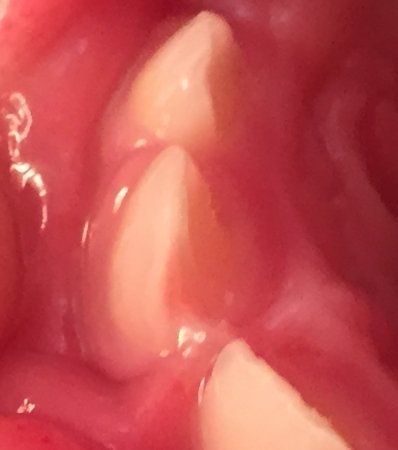

Моя дочка (2 года и 7 месяцев) недавно упала и передний верхний зуб треснул и шатается, а второй передний верхний зуб немного шатается. Кушать ей больно сейчас, десны немного опухшие. И когда упала, кровь шла долго. Ходили к врачу, сказала, что нужно удалять.

Уважаемая мама, чтобы ответить вам, необходим осмотр и рентген снимки, если подвижность существенная, то скорее всего ваш врач прав. И зубки придется удалить. Обратитесь на прием к грамотному детскому стоматологу.